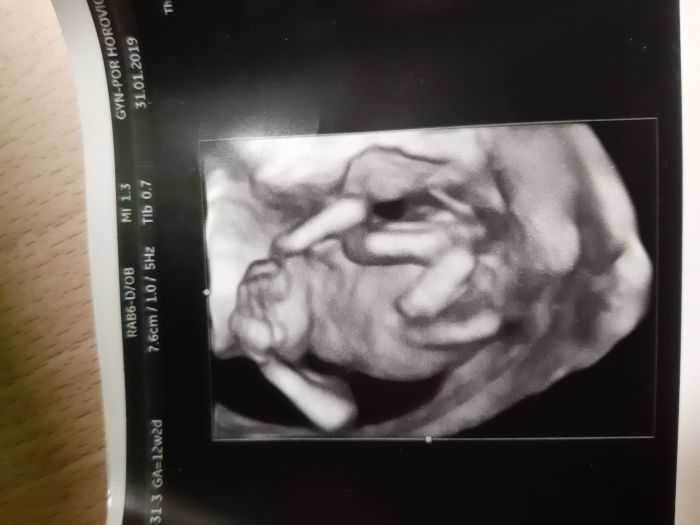

Ahojky maminky. Zajima me vas nazor. Co vidite na foto? Holcicku nebo chlapecka? Foto je cca z 22 tt. :)